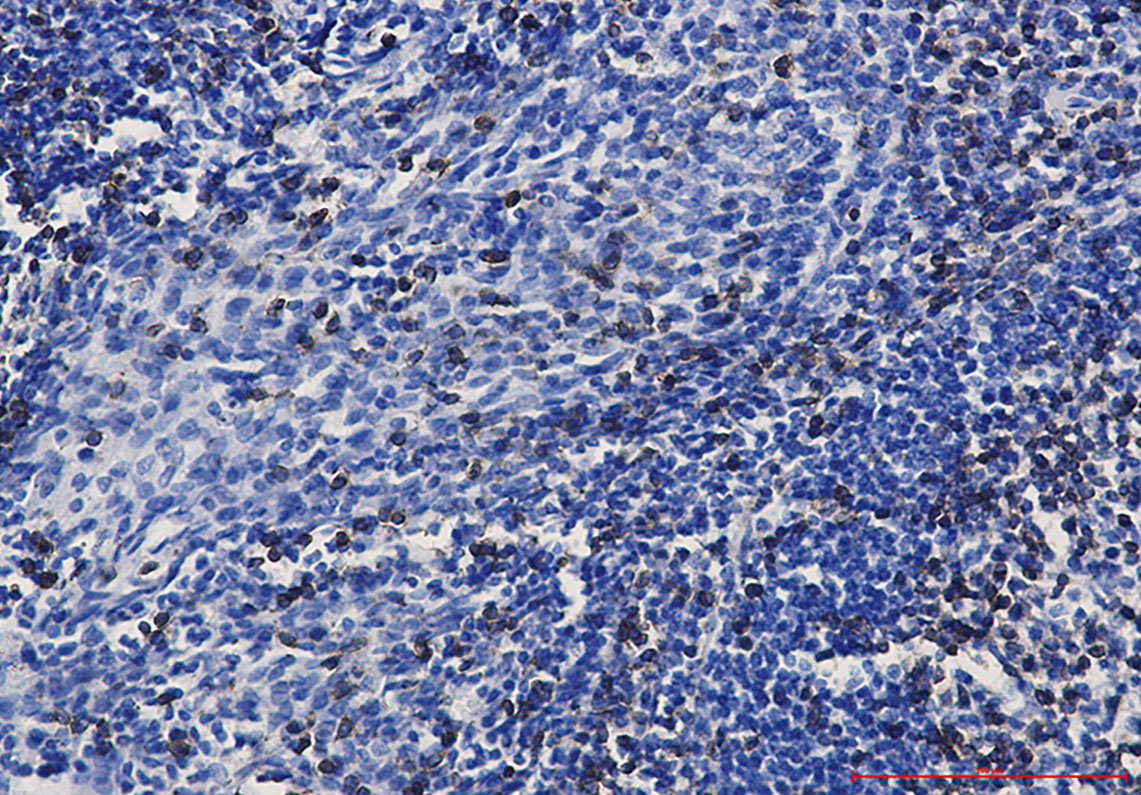

Immunohistochemistry analysis of paraffin-embedded Human tonsil using CD3 epsilon antibody.High-pressure and temperature Sodium Citrate pH 6.0 was used for antigen retrieval.